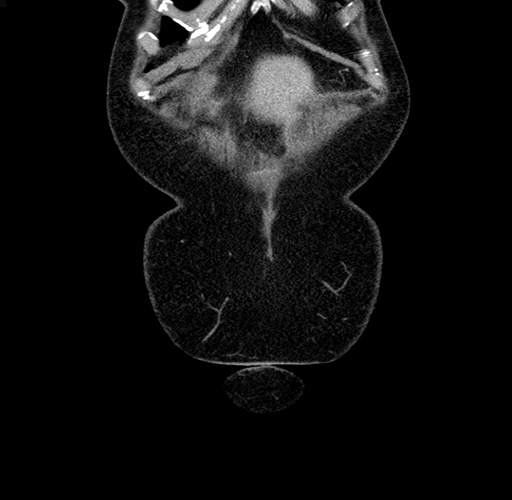

Pre-Chemo: Coronal Venous

Coronal Venous